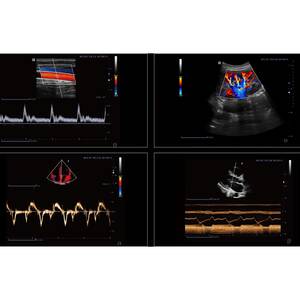

Інтелектуальний робочий процес Finus 50 Focus & Fusion:

- Auto Volume Flow — автоматизоване вимірювання площі судини та швидкості кровотоку за спектром дозволяє відобразити результати об'єму кровотоку;

Auto IMT — автоматичне визначення та вимірювання товщини комплексу інтима-медіа. Можливість вимірювання передньої та задньої стінок як лівих, так і правих судин;

fAssist — надання навчальної інформації щодо обстеження черевної порожнини, судин, дрібних органів, гінекології, м’язово-скелетної системи тощо, включаючи стандартні ультразвукові зображення, анатомічні діаграми, методику сканування та поради.